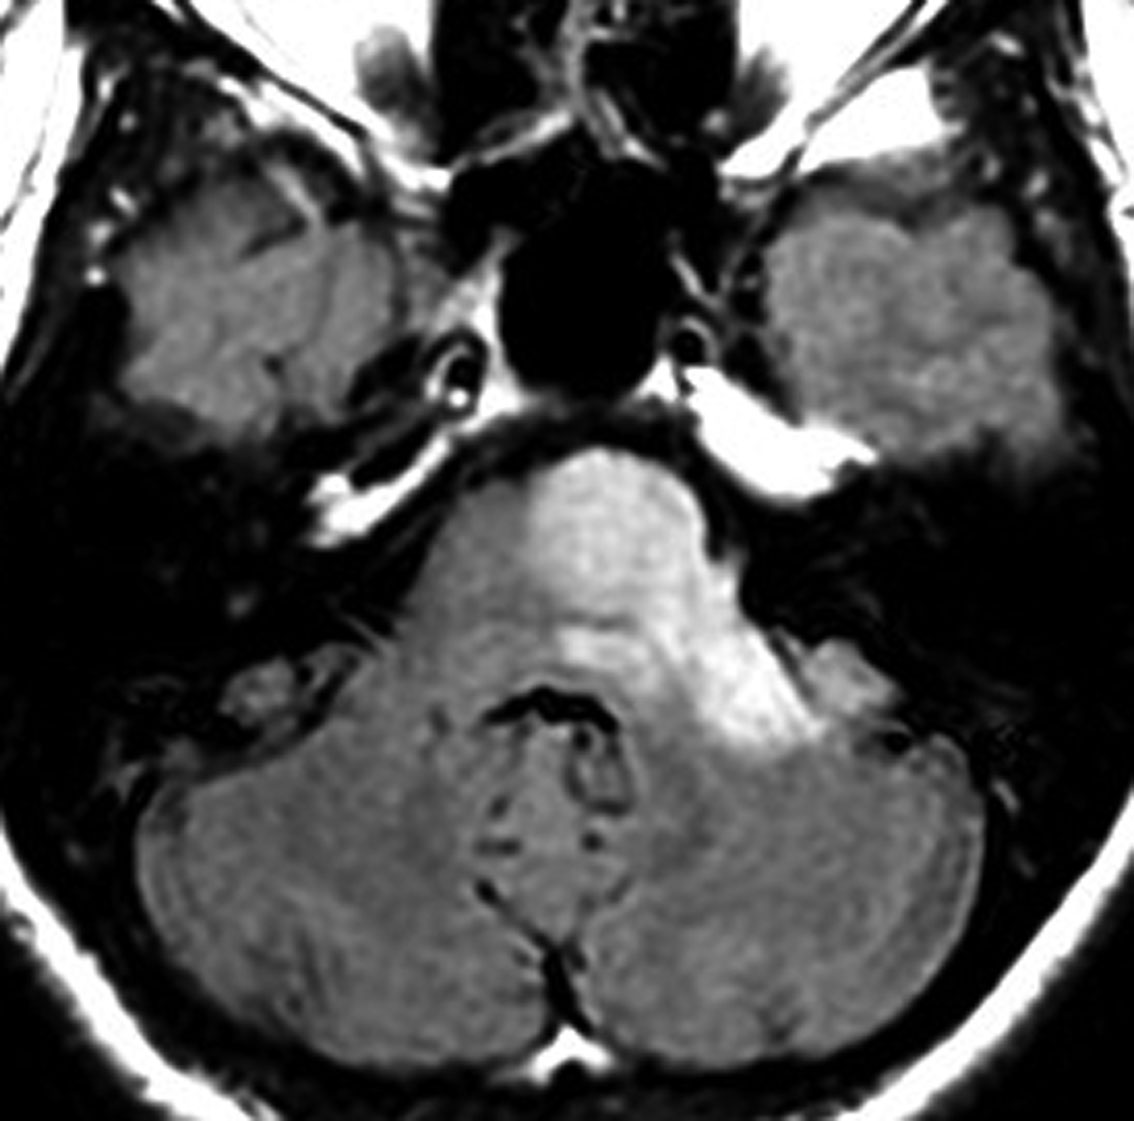

びまん性星細胞腫の画像上の3つのタイプ

実際には異なったMRI像を示す3種類のびまん性星細胞腫が知られていました。

1つ目は悪性化もしやすいし生命予後が悪いものです。かなりのものがグレード3/4と同じような臨床像を示します。脳の中心部に発生するものは,病理組織診断ではびまん性星細胞腫なのですがH3 K27遺伝子変異があり、現在は遺伝子診断で びまん性正中グリオーマ グレード4とされるものです。旧来のグリオマトーシスと呼称されたものも含みます。

2つ目と3つ目はゆっくり何年もかけて大きくなるし,手術で治る可能性もあるもので,びまん性星細胞腫といってもかなり性質が違います。古くからIDH-1/2の遺伝子変異がある星細胞腫は限局性で十分な摘出ができる可能性があるとされてきました。

1 脳深部に滲むように広範囲にあり増大速度が速いもの

2 滲むように広がって増大速度がとても「遅い」もの

3 表面にあって境界が明瞭であまり浸潤しないもの

画像所見

• CTでは,低吸収域で周囲の脳より少し黒っぽく見えます

• MRI のT2・FLAIR(フレア)画像で淡く白く見える(高信号)のが特徴です

• 一般的には,びまん性で周囲がはっきりしない脳の中に「にじむような腫瘍」に見えます

• 初期には、一つの脳回に限局して境界が明瞭な小さな腫瘍として発見されることもあります (single gyrus glioma)

• ガドリニウム造影剤で増強されることはほとんどありません

• ガドリニウムで増強された場合はグレード3以上の星細胞系腫瘍が混じっていることを疑います

• 石灰化やのう胞はあり得るのですがとても稀です

• あった場合には乏突起膠腫を疑った方がいいでしょう

• 平均すると年に6mmくらい大きくなります

• でも,ゆっくり大きくなって5年くらい見ていてもあまり大きさが変わらないものから,3ヶ月くらいで倍くらいになってしまうものもあります,油断ができません

• 島 inselを侵す星細胞腫 (insular glioma)は予後不良とされます